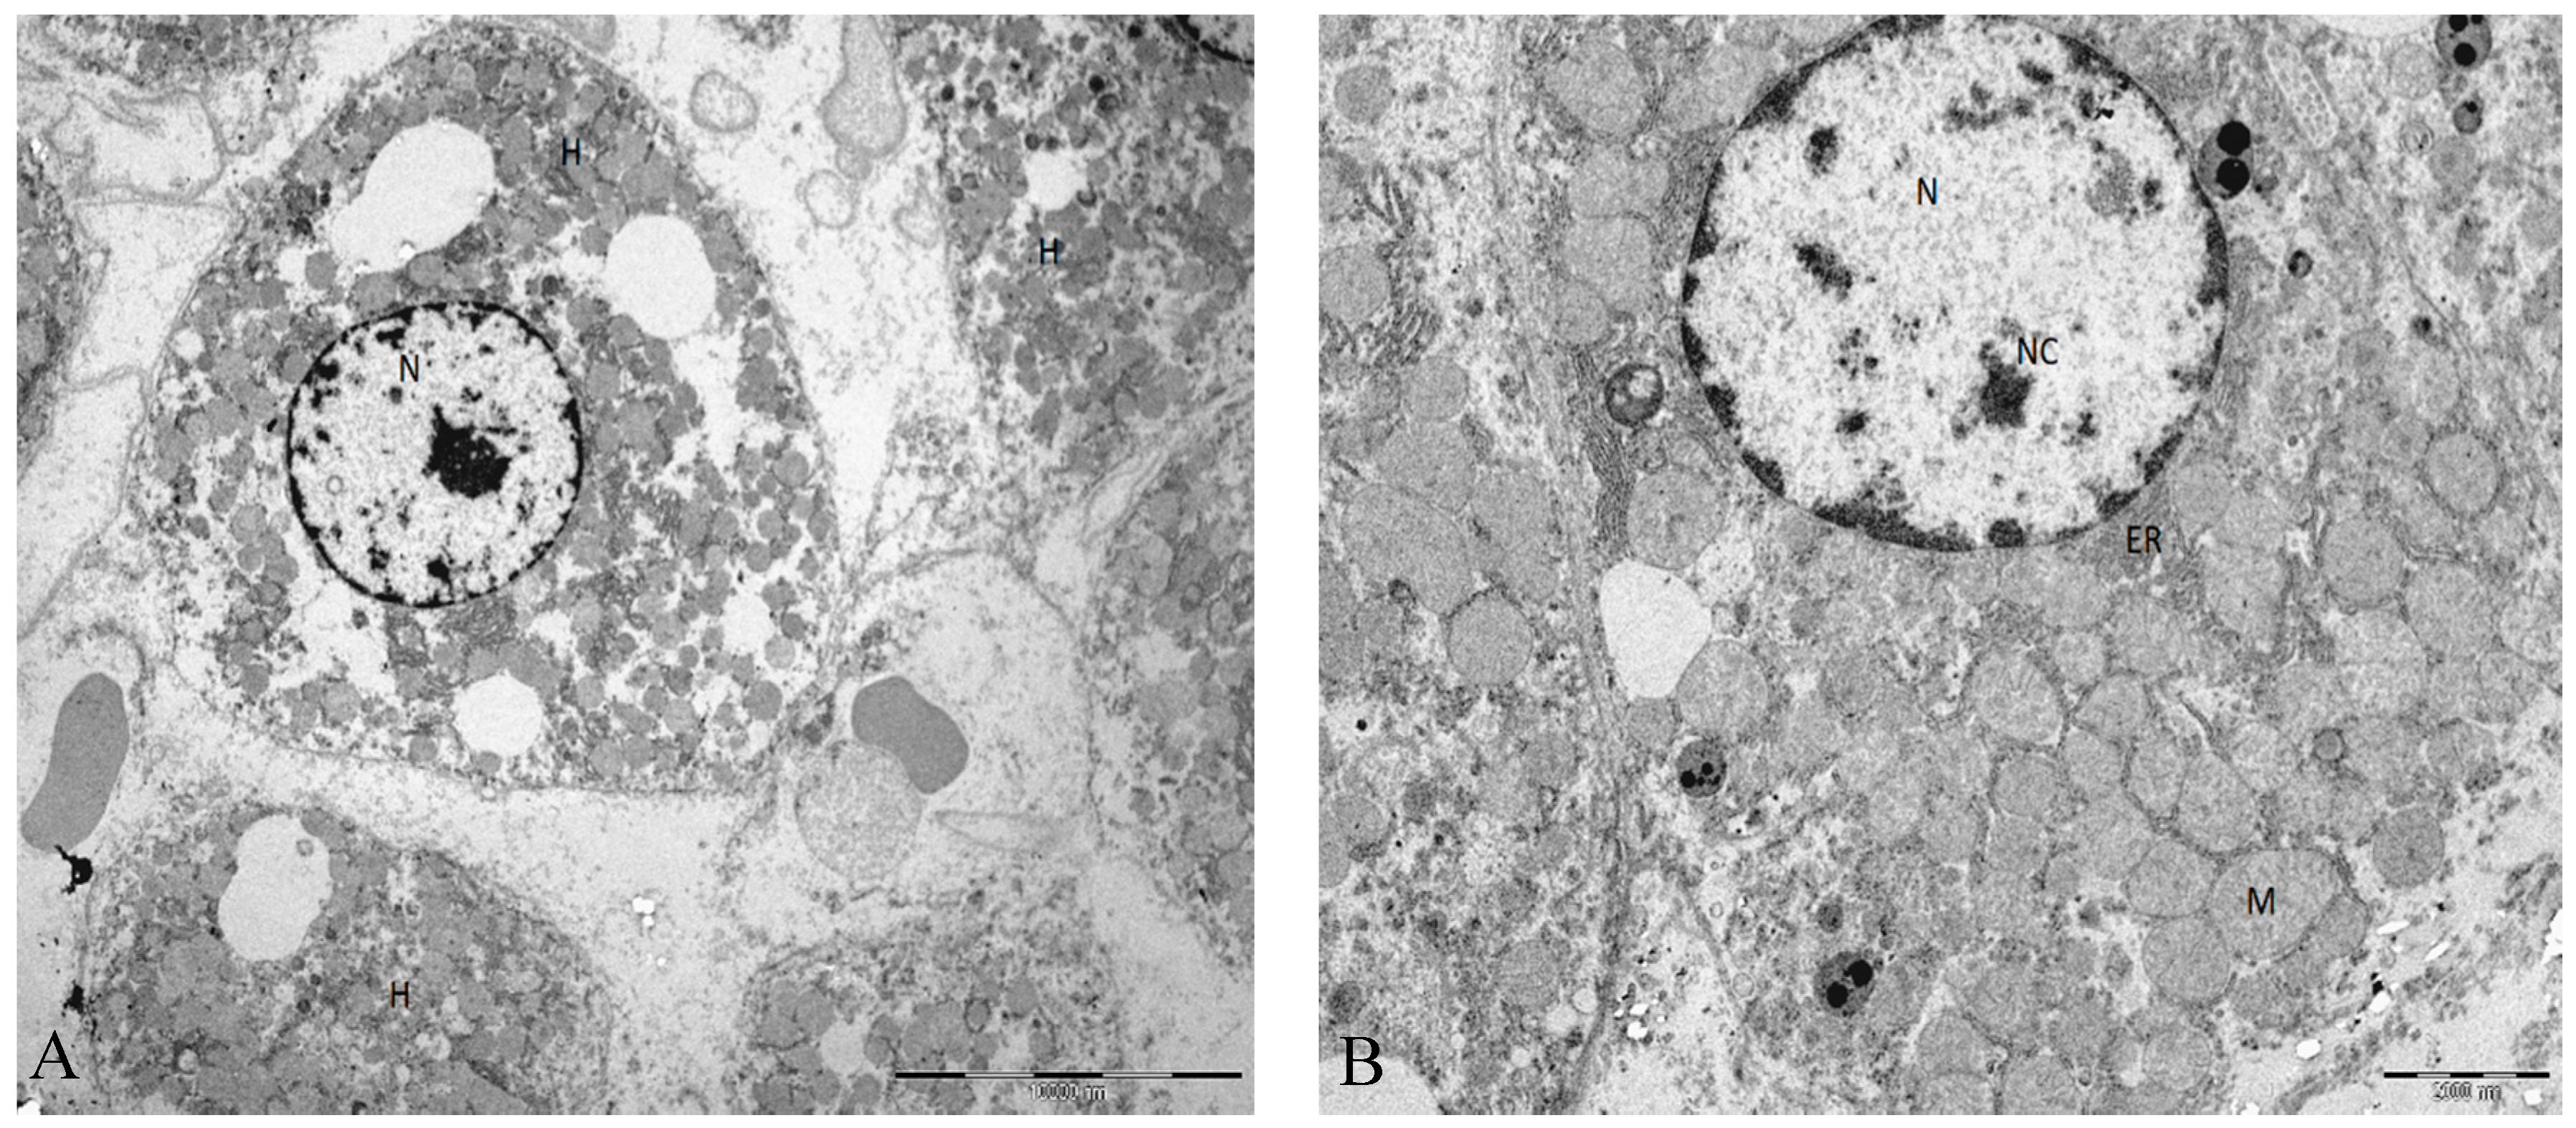

2.1. Histologic Evaluation

4.13. Transmission Electron Microscopy Analysis